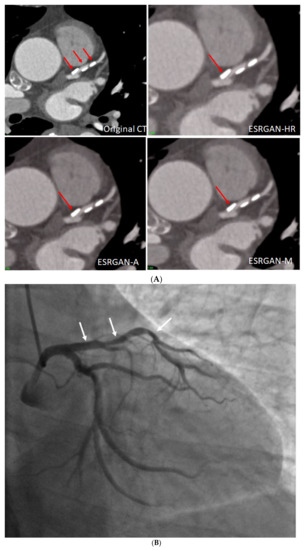

Figure 4 is an example showing multiple calcified plaques at LAD with improvement in the visualisation of coronary lumen observed in ESRGAN-processed images when compared to the original images, while Figure 5 is another example demonstrating multiple calcified plaques at RCA showing improved lumen assessment with ESRGAN-processed images.

Figure 5.

Multiple calcified plaques at the right coronary artery (RCA) in a 64-year-old man with coronary artery disease. (A): Curved planar reformatted image shows multiple calcified plaques at the RCA. Arrow refers to the plaque in the proximal RCA causing >50% stenosis that was selected for comparison of lumen differences. (B): Comparison of the enhanced super-resolution generative adversarial network (ESRGAN)-processed images with original CCTA in the assessment of coronary lumen stenosis caused by the plaque (arrows) as indicated in Figure 4A. The mean lumen stenosis was measured 59%, 52%, 48% and 47% at original CCTA, ESRGAN-High Resolution (ESRGAN-HR), ESRGAN-Average (ESRGAN-A) and ESRGAN-Median (ESRGAN-M) images, respectively. (C): Invasive coronary angiography confirms no significant stenosis with measured diameter of 33% (arrow). ESRGAN-A and M images improved the lumen assessment illustrating no significant stenosis as well.